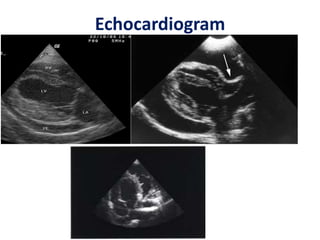

Echocardiogram

RA collapse RV collapse

• Dilated IVC with minimal

or no collapse

• Restrictive filling pattern

• Significant respiratory

variation in filling pattern

• Tamponade : equal and

continuous restriction

throughout diastole

• CP : Restriction to filling

in late diastole

Echocardiogram • Dilated IVCwith minimal or no collapse • Restrictive filling pattern • Significant respiratory variation in filling pattern • Tamponade : equal and continuous restriction throughout diastole • CP : Restriction to filling in late diastole